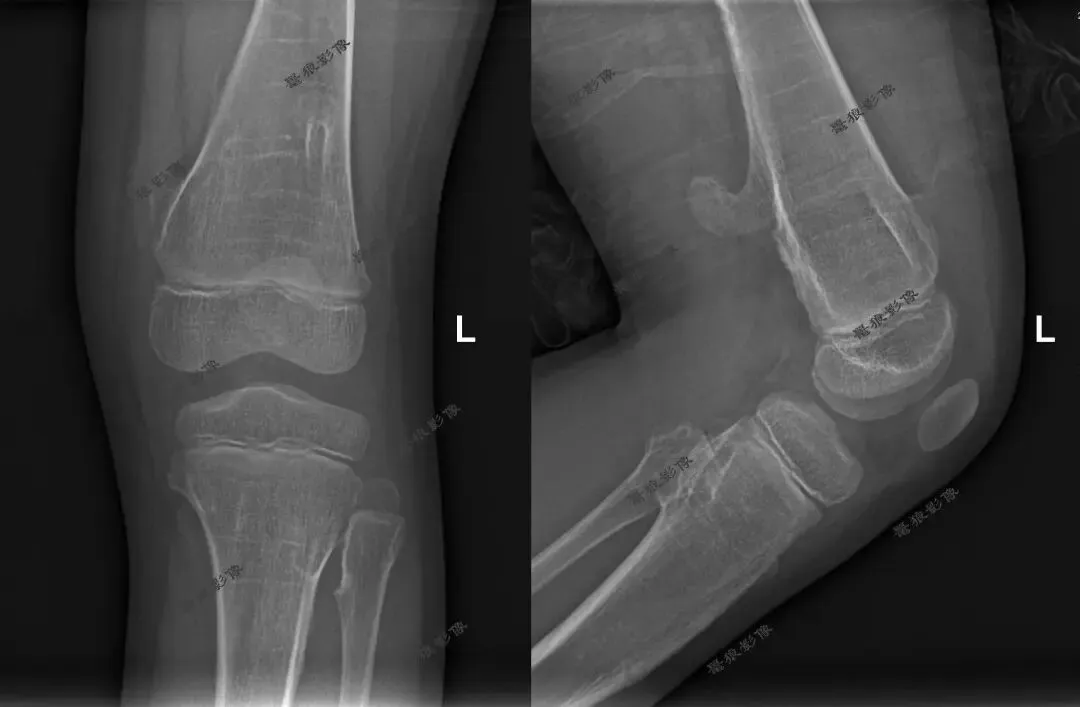

M,7y。双腕及双膝周围多处隆起就诊。

双腕关节及双膝关节X线片如下图:

考虑双腕关节及双膝关节旁多发骨软骨瘤,右膝为甚。